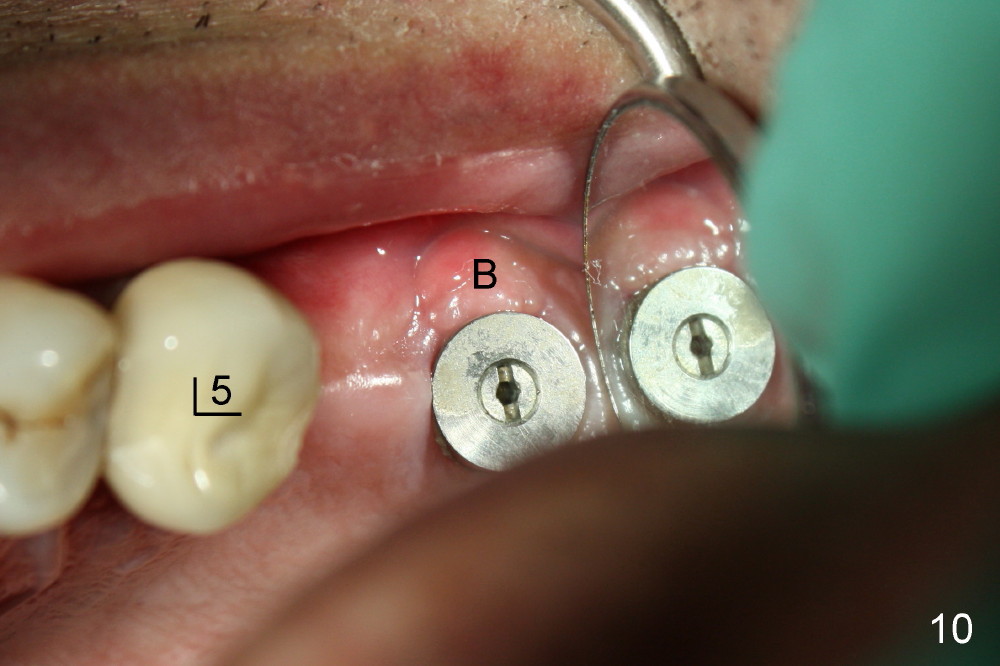

两周后郑先生也需要拔除左上第二磨牙即刻植牙(图八),植牙窝在中隔偏向颊侧开始(图七D蓝圆圈,与图七B对比),虽然植牙窝扩大过程中也逐渐向鄂侧移动,但是最后植牙基本落入拔牙窝中间(图七E粉红色圆圈,图九(术后四天),图十(术后一个月),图十一(三个月;第一磨牙植牙一周))。